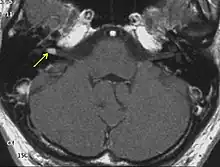

The so-called acoustic neuroma of NF2 is in fact a schwannoma of the nervus vestibularis, or vestibular schwannoma. The misnomer of acoustic neuroma is still often used. The vestibular schwannomas grow slowly at the inner entrance of the internal auditory meatus (meatus acousticus internus). They derive from the nerve sheaths of the upper part of the nervus vestibularis in the region between the central and peripheral myelin (Obersteiner-Redlich-Zone) within the area of the porus acousticus, 1 cm from the brainstem.

Bilateral vestibular schwannomas are diagnostic of NF2.[15]